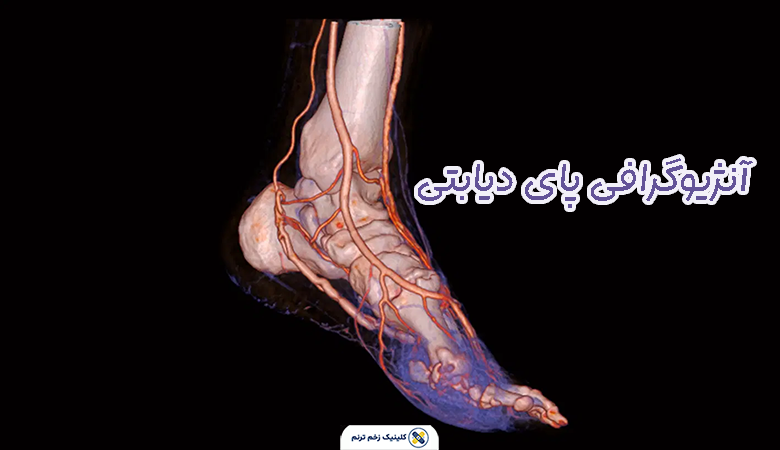

آنژیوگرافی در بیماران مبتلا به پای دیابتی، صفر تا صد تشخیص و درمان

آنژیوگرافی پای دیابتی یک روش درمانی است که در این سالها برای تشخیص و درمان پای دیابتی استفاده میشود. در این روش با عکسبرداری از رگهای پا در بیماران دیابتی، دکتر میتواند گرفتگی رگها را تشخیص دهد.

آنژیوگرافی در درمان پای دیابتی اهمیت زیادی دارد، زیرا با ارائه تصویربرداری دقیق از عروق خونی پا، میزان و محل انسداد رگها را مشخص میکند و به پزشک امکان میدهد که بهترین روش بازسازی عروقی را انتخاب کند.